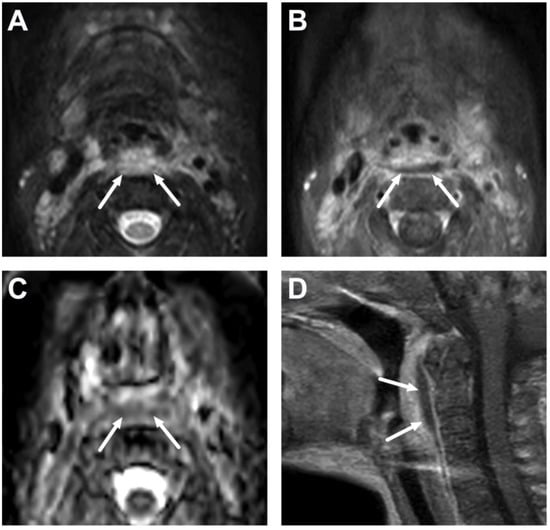

6.1. Mediastinitis

6.2. Venous Thrombosis